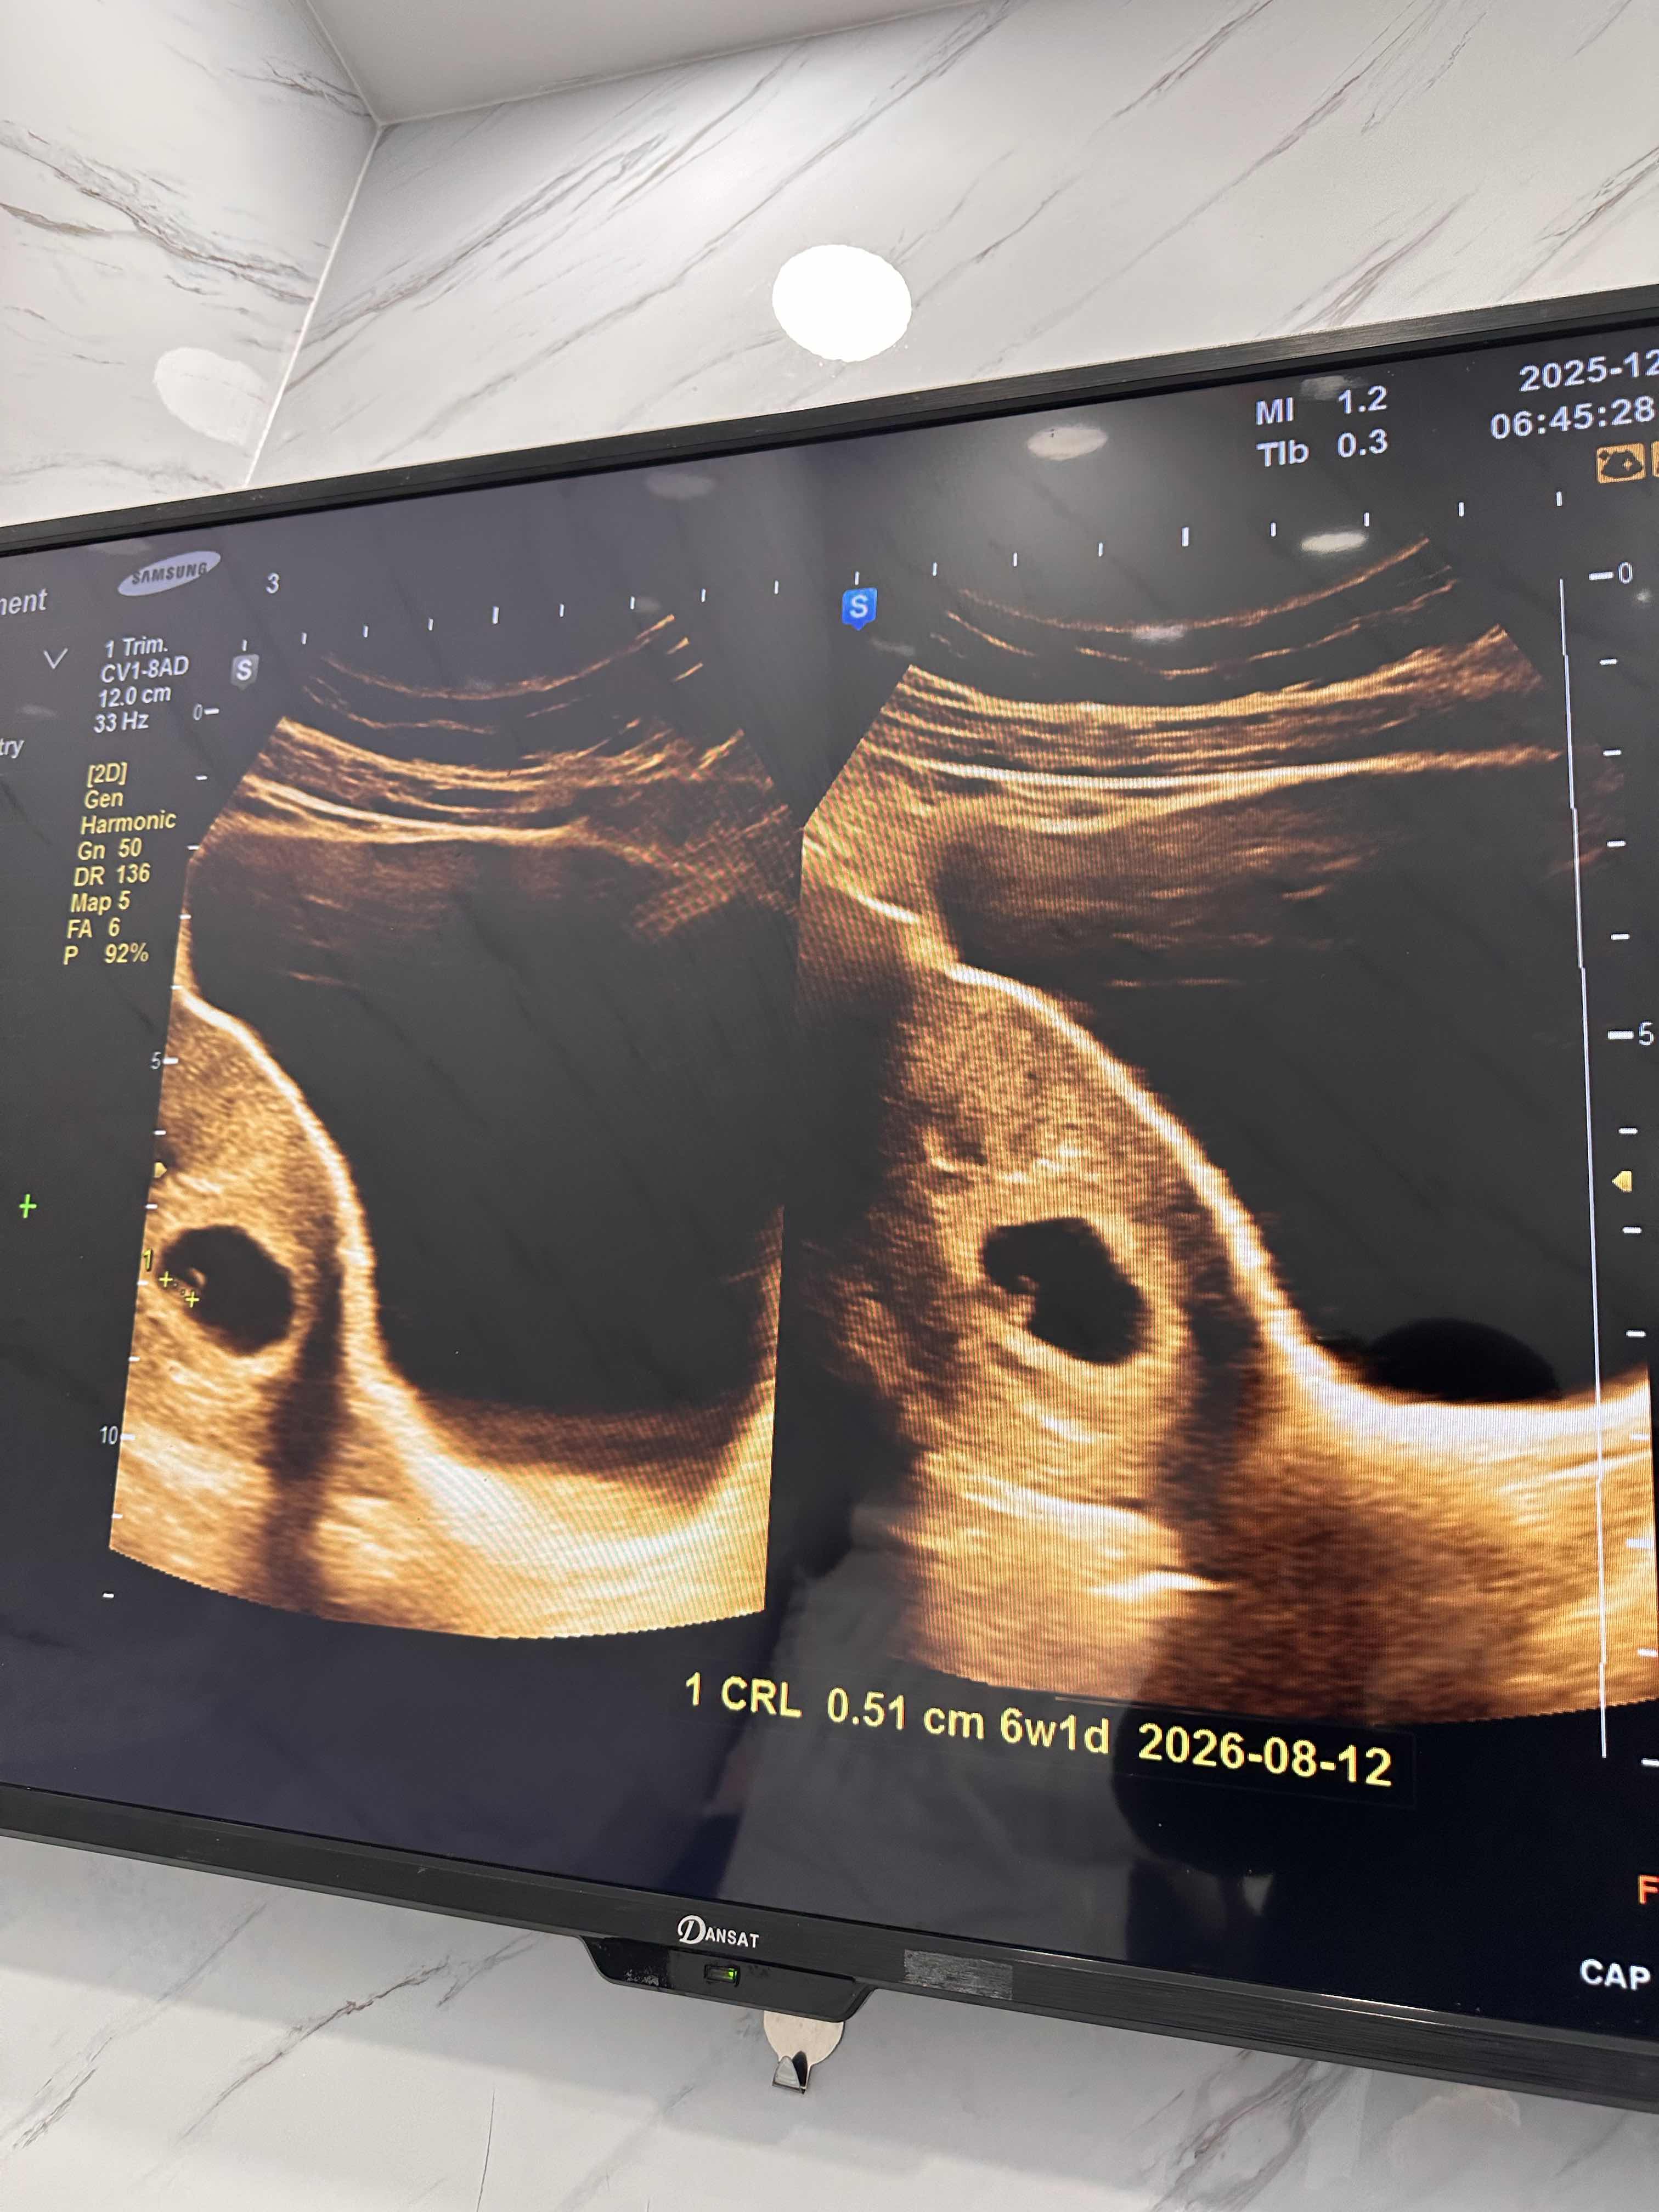

حامل في الاسبوع السادس والجنين نازل